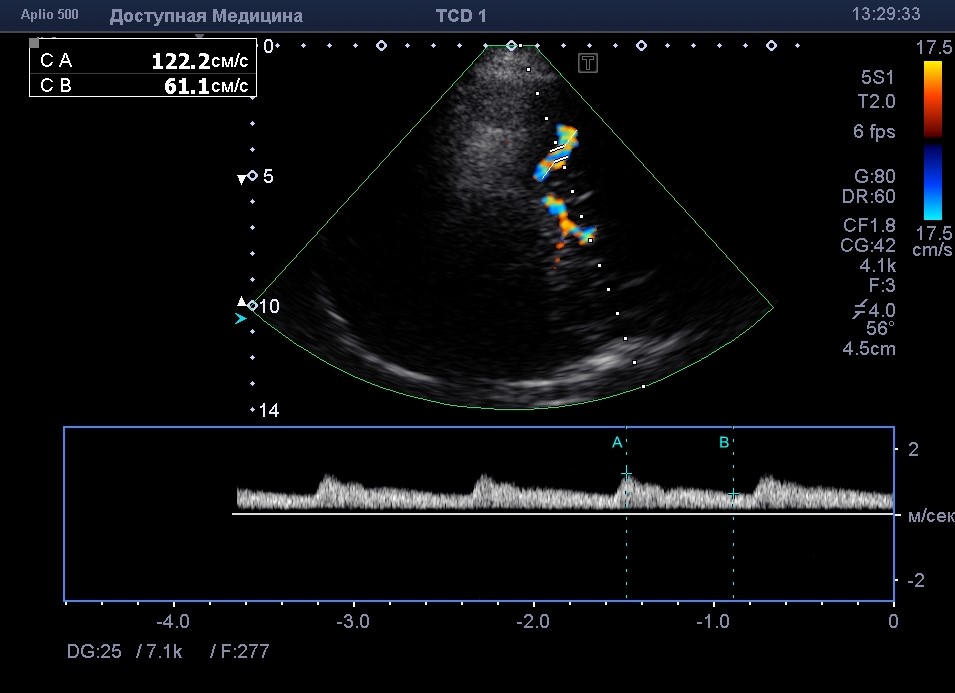

На ультразвуковом аппарате представляется возможность, в различных режимах и настройках аппаратуры оценить состояние кровотока в исследуемом сосуде. Также, представляется возможным найти патологическое образование вблизи анатомической проекции сосуда или выявить патологические изменения в артериях (аневризму, стеноз, тромбоз). Стоит отметить, что УЗ метод исследования может затрагивать, только поверхностно расположенные сосуды и не нуждается в статичной фиксации пациента, в отличие от КТ и МРТ.

В клинической практике МР-ангиография является скрининговым методом и только лишь при выявлении каких-либо патологических изменений в сосудах или близлежащих тканях назначают КТ-ангиографию, которая позволяет более детально изучить найденную патологию. УЗ метод является дополнительным и помогает оценить состояние кровотока.